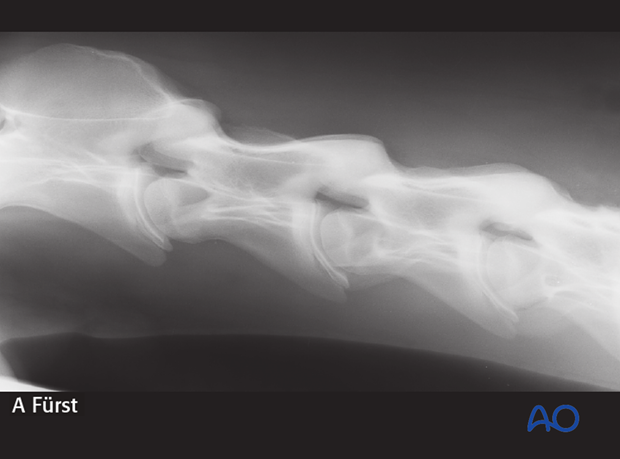

1.5-year-old Warmblood foal with instability of C3-C4-C5.

The instability is not visible on straight lateral radiographs.